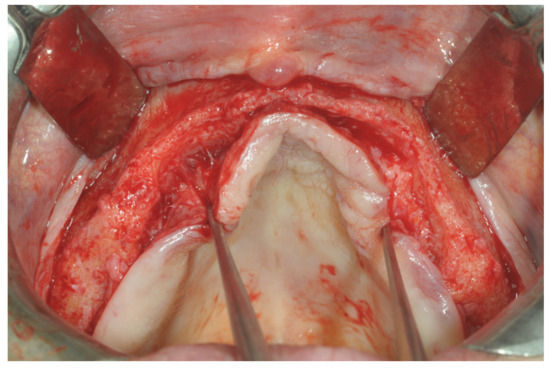

Patients rinsed with a chlorhexidine mouthwash (0.2%) for 1 min immediately prior to the intervention. Local anesthesia were administered using mepivacaine with adrenaline at ratios of 1:100,000 or 1:50,000. Crestal incisions were made with releasing incisions far away from the future membrane positioning and full thickness flaps were elevated. After the meticulous removal of all residual soft tissues in the regenerating site, copious bleeding was induced using a bone scraper (Safescraper Curve TWIST, META, Reggio Emilia, Italy) (Figure 1). A prosthetically guided implant placement was performed following the instructions of manufacturer (Thommen Medical, Grenchen, Switzerland). Only 1 patient had implants placed 9 months after bone augmentation because the initial bone thickness did not permit the primary stabilization of the implant fixtures (Figure 2, Figure 3, Figure 4, Figure 5, Figure 6, Figure 7 and Figure 8).

Figure 1. Graft recipient area after bone decorticalization and distal fixation of the non-resorbable barrier.